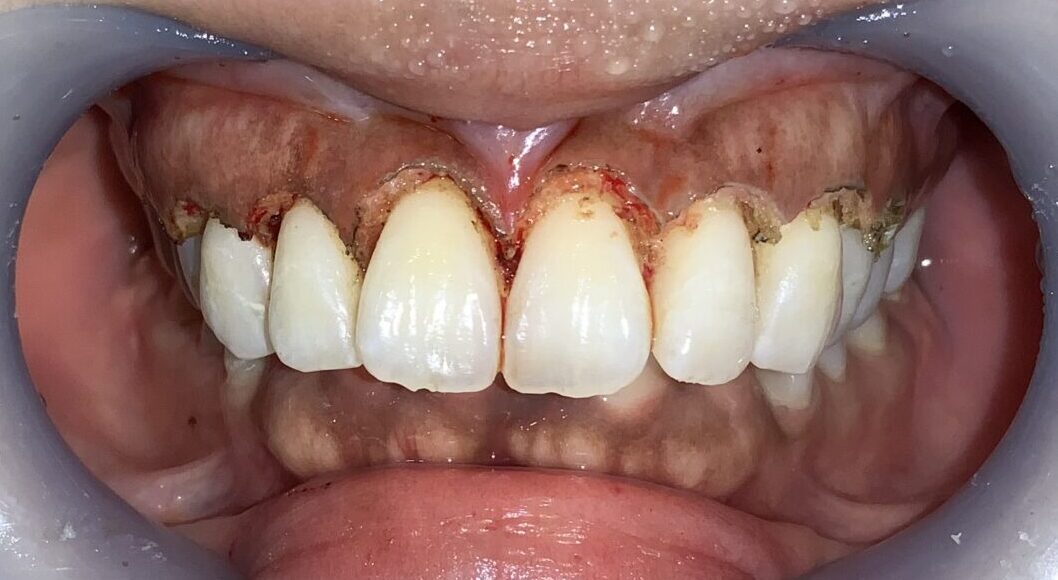

まずは1本だけ歯ぐきの整形を行なって、患者様に確認をして頂きます。

歯ぐきの面積が小さくなり、歯が大きくなり、歯ぐきの形が整っています。

このように歯槽骨整形も一緒に行なって、綺麗な歯槽骨になったので、後戻りの心配がなくなり、しかも綺麗に仕上がります。

片側だけ終わりました。患者様にも確認をして頂きます。歯ぐきの形、歯の形、笑った時の歯ぐきの見え方を全てご確認頂きました。

患者様にも仕上がりに納得して頂きました。

反対側の歯も全て整えました。